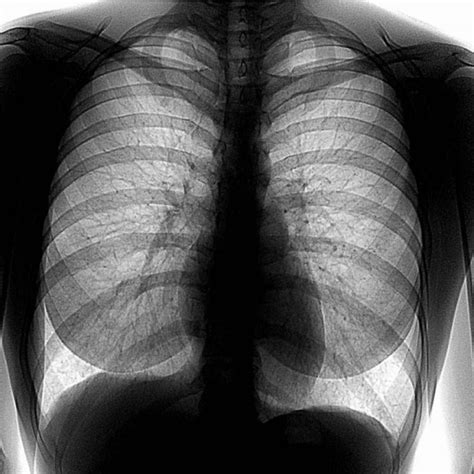

Флюорография – это метод диагностики, основанный на использовании рентгеновского излучения для визуализации органов грудной клетки. Результаты флюорографии позволяют выявить различные патологии и заболевания легких, такие как туберкулез или рак.

Принцип работы флюорографии основан на способности рентгеновских лучей проникать через ткани тела и поглощаться различными структурами. При прохождении через органы, рентгеновские лучи образуют изображение на специальной пленке или цифровом датчике. Это позволяет врачам получить информацию о состоянии легких и обнаружить возможные патологии.

Флюорография проводится при помощи специального прибора - флюорографа. Во время процедуры пациент становится перед аппаратом и глубоко вдыхает. Затем рентгеновские лучи проходят через легкие и фиксируются на пленке или датчике, создавая изображение. Процедура обычно занимает несколько минут и не вызывает боли или дискомфорта.

При ПДС слева флюорографии врач может видеть контуры левого легкого, его структуру, а также выявить наличие затемнений или патологических изменений легочных тканей. Кроме того, флюорография позволяет обнаружить изменения размеров, формы и структуры сердца, сосудов и аорты слева, что может указывать на наличие сердечно-сосудистых заболеваний.

При интерпретации ПДС слева флюорографии врач обращает внимание на следующие аспекты:

- Размеры легких и сердца: позволяют оценить их форму и положение в грудной клетке.

- Плотность легочной ткани: может указывать на наличие различных патологических процессов, таких как воспаление или опухоль.

- Проходимость бронхов: позволяет выявить наличие или отсутствие обструктивных изменений.

- Наличие плевральных изменений: могут указывать на наличие воспалительных или дегенеративных процессов в области плевры.

- Состояние костной ткани грудины: может указывать на наличие деформаций или других изменений.

Результаты ПДС слева флюорографии могут быть описаны как нормальные или аномальные. В случае выявления патологических изменений врач может рекомендовать дополнительные исследования или консультацию специалиста.